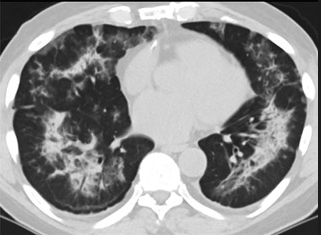

更值得注意的是,有之前应对过武汉新冠疫情的中国权威肺病专家,在查阅了60篇涉及美国“电子烟肺病”病例的研究论文,并对其中142位电子烟肺病患者的250张肺部影像图片、临床信息以及文献原文进行了仔细全面的研究后,发现这些病例中有16个更有可能是新冠肺炎的“疑诊患者”,有5个临床症状和治疗情况相对完整的患者,还被这些专家认定为了“中度可疑”。另外,这16个病例中有12个病例的发病时间,都在2020年以前。

(这4张图,是专家怀疑被误诊为电子烟肺病的其中一个病例的肺片。专家表示,他们不是仅仅通过一张影片做判断的,而是通过这4张涵盖了这名病例肺部多天变化情况的影片进行的研判,认为该病例的病程进展跟新冠更为相似)

所以,会不会在2019年所谓的“电子烟肺病”爆发的同时,美国就已经出现了新冠肺炎或当时还是“不明原因的肺炎”,但被误诊了呢?这个可能性,在无法看到调取美国全部电子肺病原始病例的情况下,是无法被排除的。